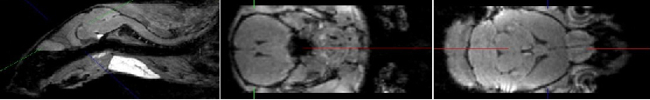

b) Small Animal MRI

Christian Kremser

In addition to clinically oriented projects, the Department of Radiology conducts experimental MR examinations on various animal models and specimens. Over the years, coil setup and imaging sequences have been optimised accordingly. Study topics include: mouse spinal cord imaging after shock wave treatment to promote spinal cord repair; volumetry of mouse myocardium to quantify fibrotic changes after constriction of the aorta and pulmonary artery; volumetry of the mouse brain to quantify fixation shrinkage; pulse wave velocity imaging in rabbits to evaluate aortic plaques; volumetric quantification of subcutaneous and visceral fat in mice on different diets; detection of intervertebral disc herniation in knockout mice.